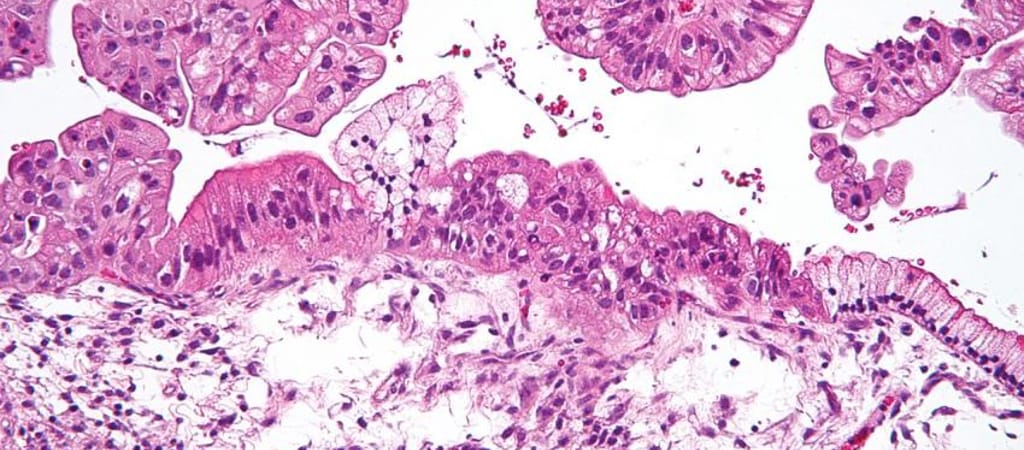

A kutatók 2004 és 2015 között diagnosztizált 364 petefészekrákos nő szövetmintái és CT-felvételei alapján matematikai szoftverrel állapították meg, mennyire agresszív egy-egy daganat. A szoftver a tumor négy biológiai jellemzőjét – szerkezetét, alakját, méretét és genetikai profilját – vizsgálta meg, ennek alapján állította fel a prognózist.